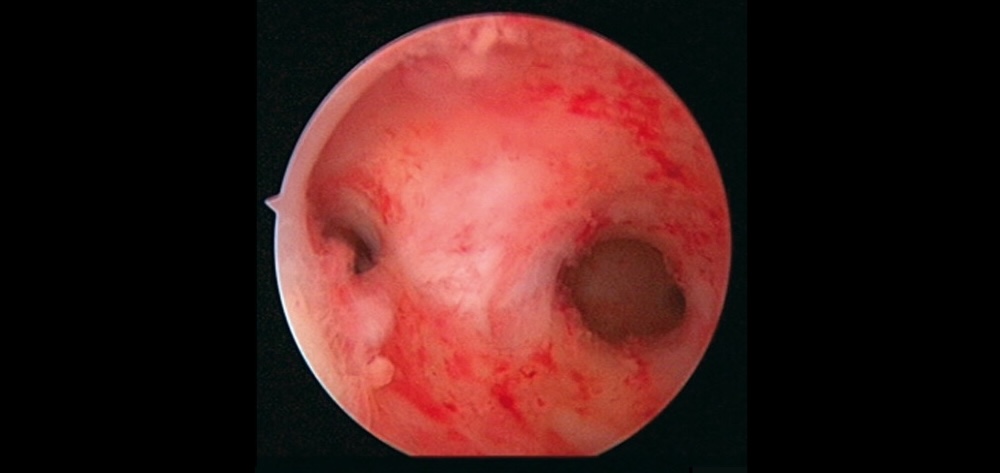

- Histeroscopía diagnóstica (método de elección)

La histeroscopía permite visualizar directamente la cavidad uterina y evaluar el grado de las adherencias.